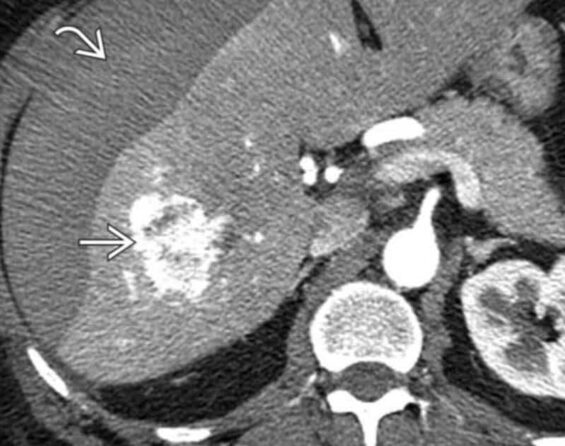

Until recently, the therapeutic options for patients with advanced hepatocellular carcinoma (HCC) were very limited.